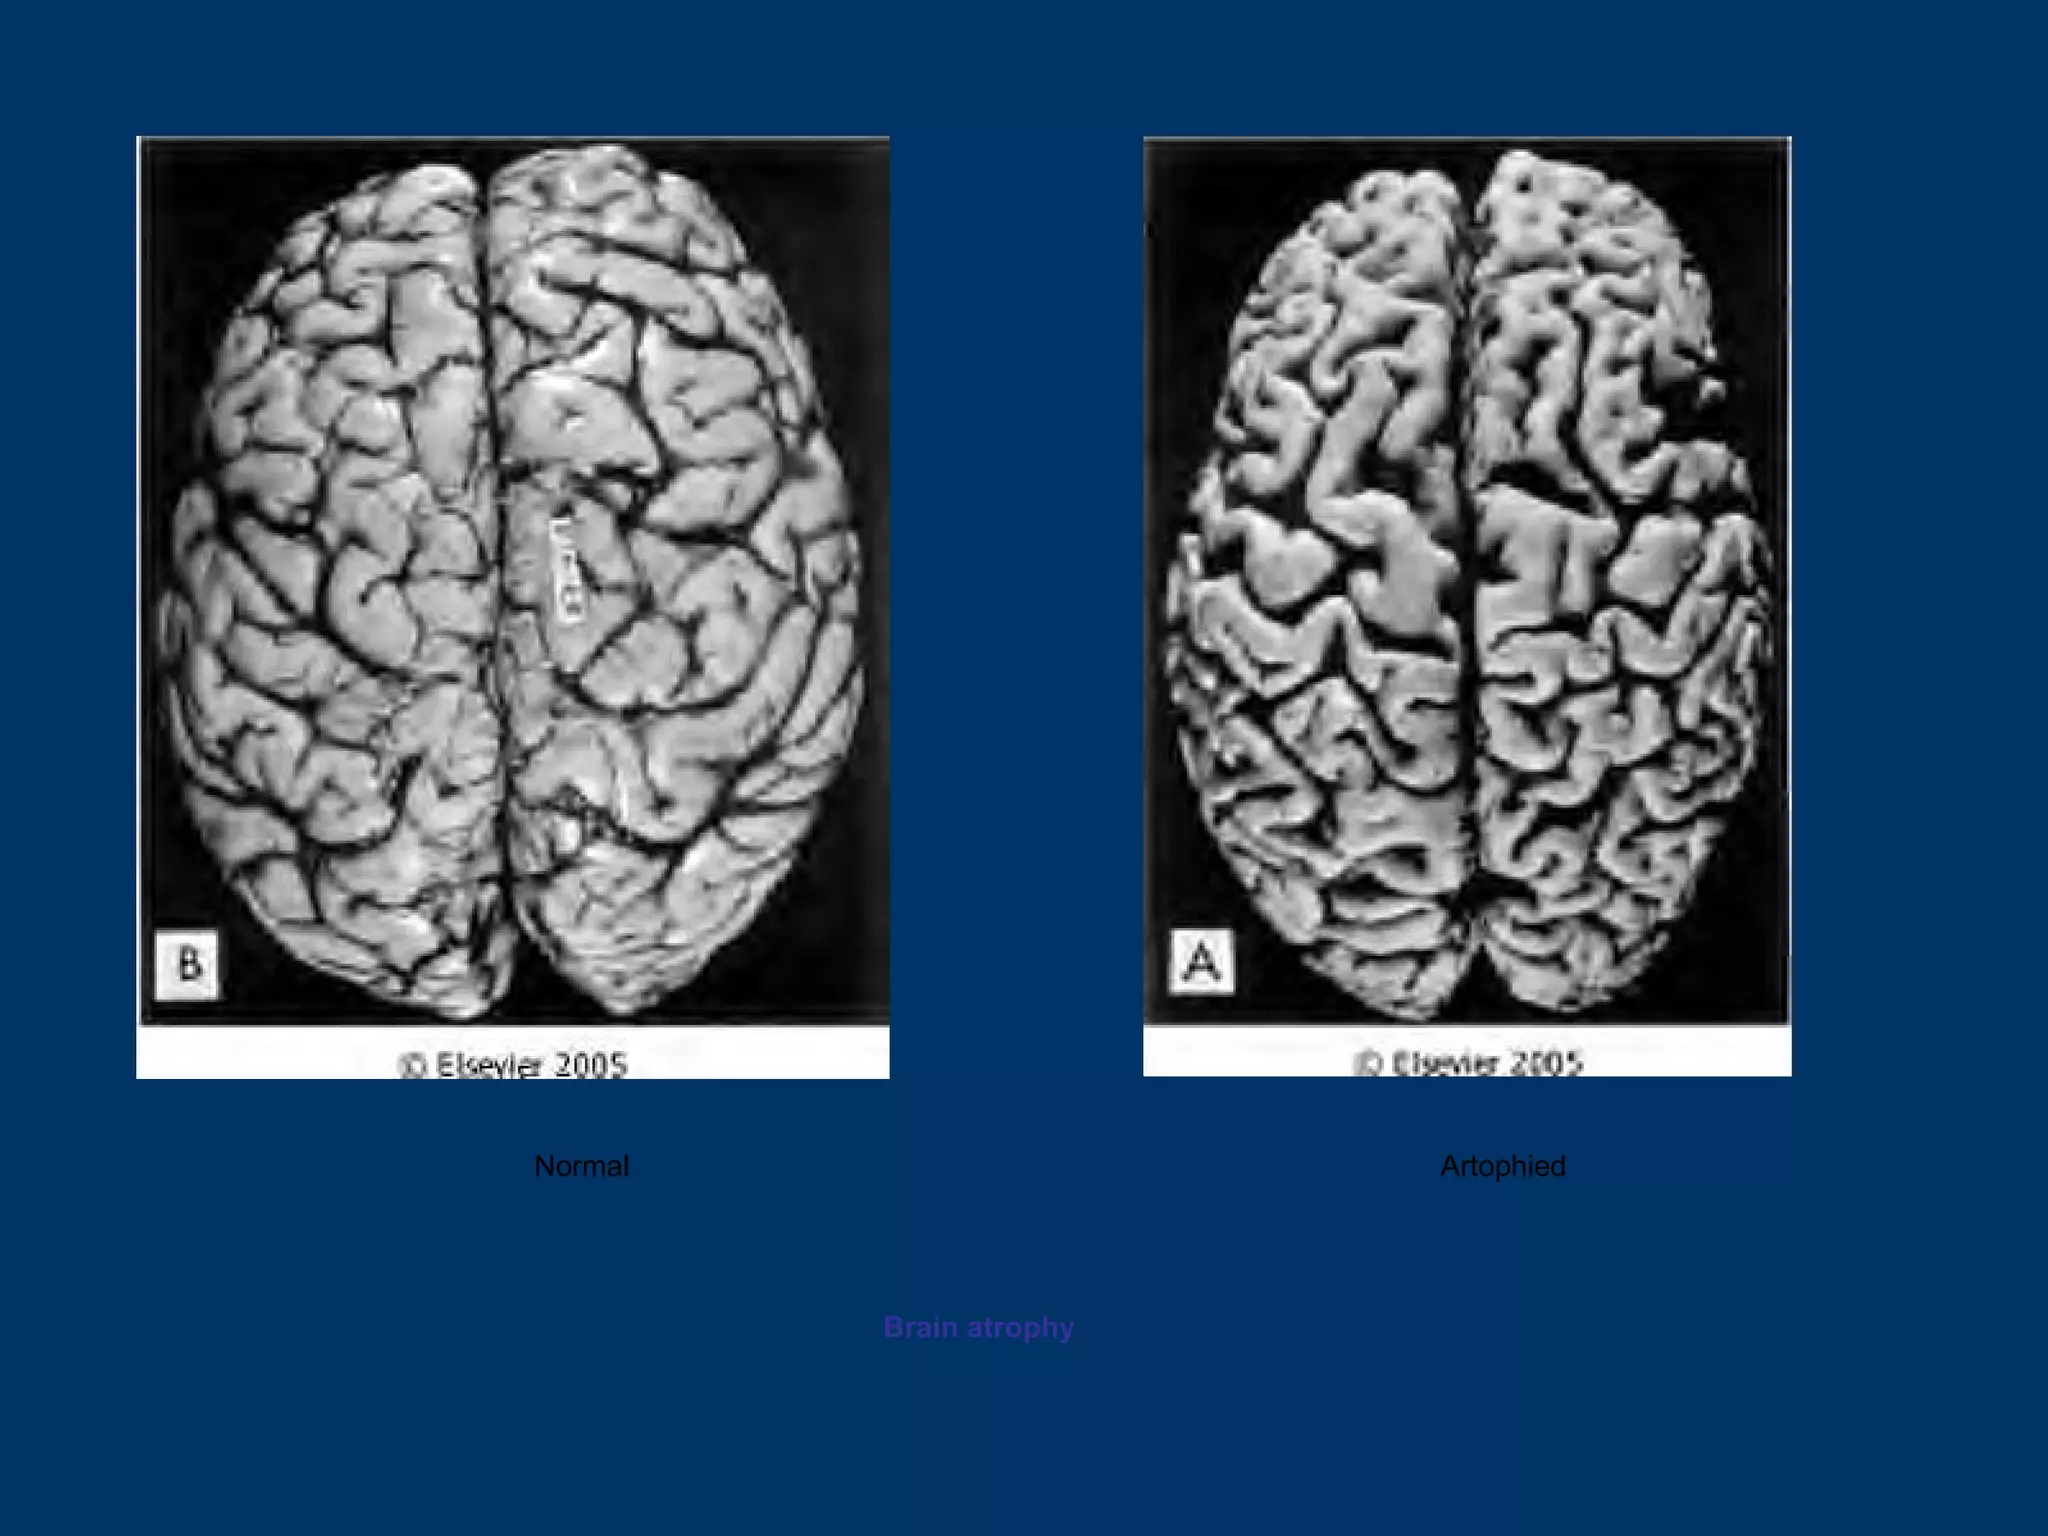

CORTICAL ATROPHY

Normal                   Artophied

Brain atrophy

Normal Artophied Brain atrophy